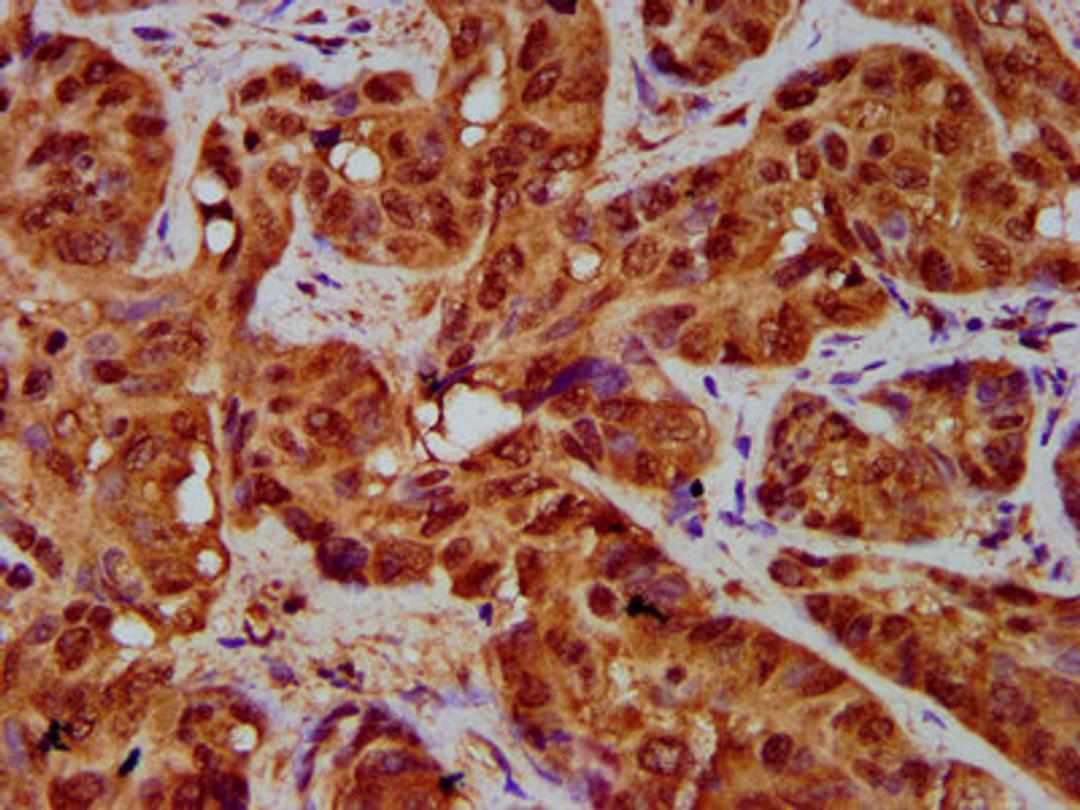

IHC image of CSB-PA14729A0Rb diluted at 1:200 and staining in paraffin-embedded human liver cancer performed on a Leica BondTM system. After dewaxing and hydration, antigen retrieval was mediated by high pressure in a citrate buffer (pH 6.0). Section was blocked with 10% normal goat serum 30min at RT. Then primary antibody (1% BSA) was incubated at 4°C overnight. The primary is detected by a biotinylated secondary antibody and visualized using an HRP conjugated SP system.